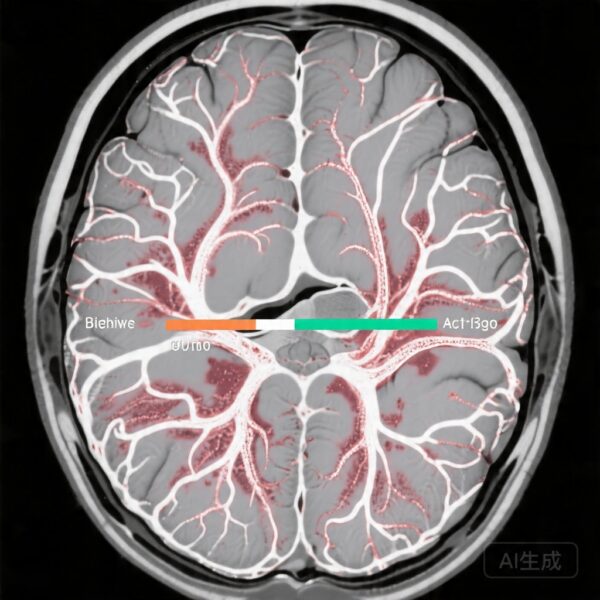

Resting-State Functional Connectivity

Resting-state fMRI analysis uncovered meaningful differences in network integration following the intervention period. The contingent neurofeedback groups (both stroke and healthy controls) exhibited greater integration among motor, auditory, and language networks, suggesting enhanced communication within distributed neural systems supporting sensorimotor integration and language processing. The noncontingent stroke group, conversely, demonstrated more disorganized connectivity patterns, with significant between-group differences confirmed by permutation testing (P=0.01) and small but meaningful effect sizes for connectivity changes (Δr=-0.1 to 0.1).

These findings align with theoretical models emphasizing that effective neuromodulation should enhance the coherence and functional integration of task-relevant networks rather than simply increasing regional activation in isolation. The specificity of connectivity changes to the contingent feedback conditions supports the mechanistic importance of the contingent relationship between brain activity and feedback presentation.